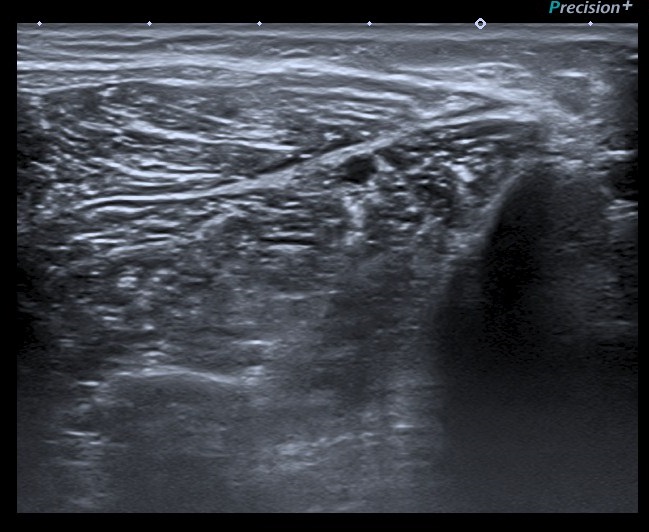

Durante la exploración del hombro me encontré un hallazgo que bien por la experiencia o por la intuición, quizá ambas, busco en cada protocolo de hombro que hago y que es punto de dolor irradiado habitual del hombro justo donde el radial pasa por la parte posterior del húmero antes de buscar la cara antero lateral externa del codo, encontrándome estas imágenes que te comento semiológicamente y que son típicas de neuropatía.

En el lugar comentado anteriormente, encuentro una estructura hipoecogénica que no es compatible con la normalidad de un nervio, como si lo es la imagen 6A que te enseño a continuación donde el nervio radial contralateral te dice cómo es un nervio radial normal en el mismo punto que el de la imagen 6, mira:

El corte longitudinal del nervio afectado es muy llamativo, tanto en su aspecto ecográfico como en su tamaño y puedes verlo en las imágenes 7 y 8.

Finalmentes la imágenes 10 y 11 donde vas a ver una comparativa en eje corto y eje largo donde vas a ver el lado derecho del paciente patológico y el lado contralateral, normal. Observa y compara, el aspecto y el tamaño y vas a ver como es más que evidente un cambio en la ecogenicidad de la ecoestructura del nervio llegando a ser el doble de grande y mucho más hipoecogénico.